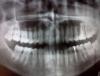

Stomart Опубликовано 18 августа, 2012 Поделиться Опубликовано 18 августа, 2012 Лучше выкладывать сами снимки, а не распечатки. Плюс у вас большая полость в шестом нижнем слева. Ссылка на комментарий

Airport Опубликовано 19 августа, 2012 Автор Поделиться Опубликовано 19 августа, 2012 (изменено) К сожалению, боли от горячего характерны когда часть нерва уже погибла.Так что, вероятнее всего,нерв(или его остатки)удалять придётся,чтобы воспаление не пошло дальше за верхушку корня. возможно ли наиболее точно выявить проблемный зуб.? ведь рентген как понимаю покажет только при запущеном осложнении... 6 чувствительна к надкусыванию сильнее , 7 на постукивания. Лучше выкладывать сами снимки, а не распечатки. Плюс у вас большая полость в шестом нижнем слева.да снимки зделаю6 слева низ.а можно узнать какой грамотный протокол должен быть для его лечения? Изменено 19 августа, 2012 пользователем Airport Ссылка на комментарий